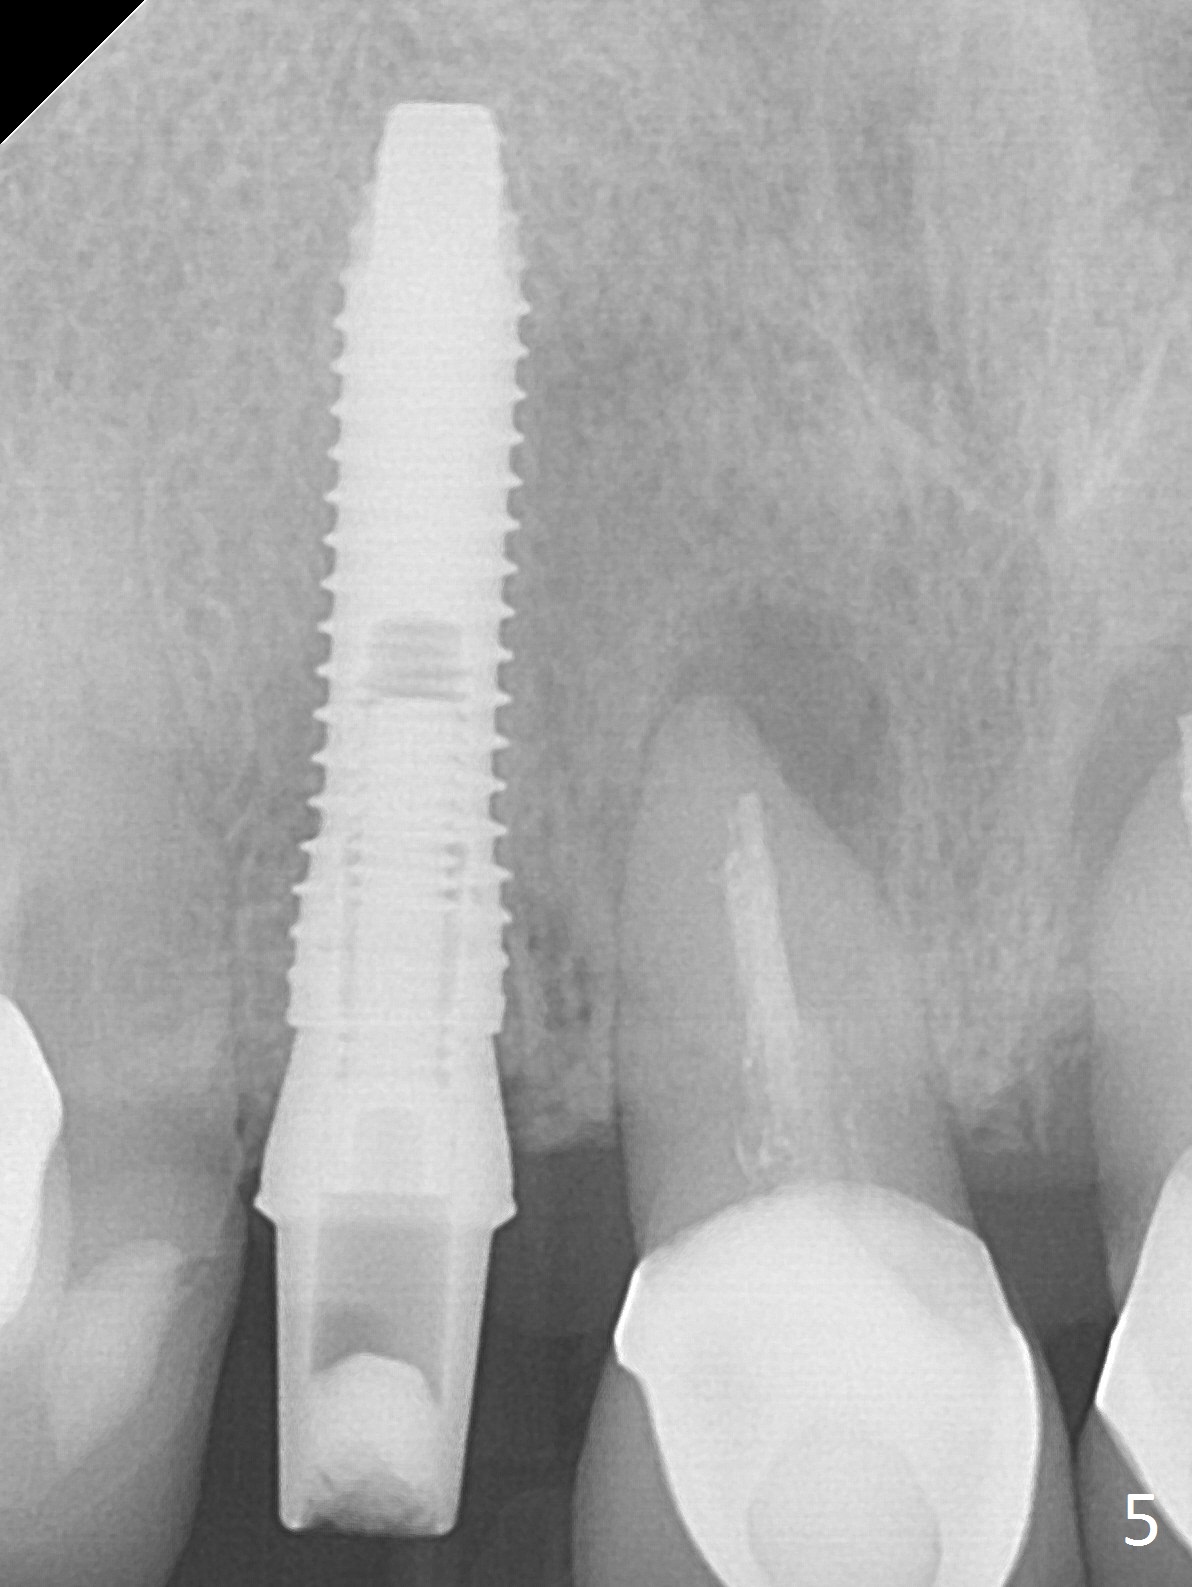

In fact the residual root (Fig.3) is easy to remove. A 3.8x16 mm implant is placed (Fig.4 (with 2 mm buccal gap)) at the level as planned (Fig.2). Insertion torque is acceptable. After placing a 4.5x5(3) mm gold-coated abutment and allograft (Fig.5), an immediate provisional is fabricated (the existing crown is lost). The patient is pleased with the quick, painless procedure.

She returns for impression 4 months postop; the abutment margin is substantially subgingival (Fig.6 arrow). The abutment is changed to 4.5x4(4) mm one before impression. There is no bone resorption 9 months post cementation (Fig.7).